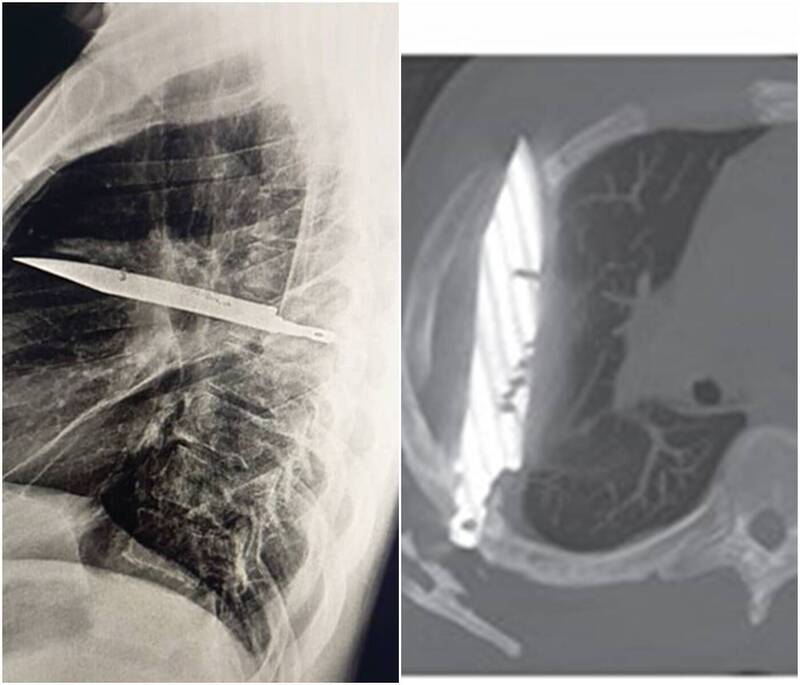

(多多马15日综合电)坦桑尼亚的一名男子因为右边乳头流脓疼痛不已而就医,因为只有乳头流脓并无其他症状让医师十分困惑,没有想到经过详细的检查过后,发现男子体内胸腔处插着一把刀,这把刀已在他体内8年。

综合外媒报道,这名44岁男子因为乳头流脓而到医院就诊,医生初步检查发现男子并无胸痛、呼吸困难、咳嗽,生命体征也都在正常值,让医疗团队非常困惑,不过在照过X光后,发现有一把刀从男子右肩胛骨插入,停留在胸腔中,男子才想起来

8年前曾跟人发生肢体冲突,在冲突的过程中被刺多刀,当时医生有做医疗处置,8年来也都正常生活,直到最近乳头流脓。

医生赶紧安排手术,将这把刀刃小心取出,并将周围坏死的组织与脓液清理乾净,术后男子在加护病房观察24小时后,转至一般病房住院10天,这起神奇的案例之后也登上《外科病例报告期刊》(Surgical Case Reports)。报告声称男子恢复良好,后续检查也没有其他异常。